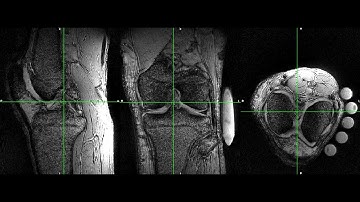

3D Dual-echo Ultra-short Echo Time MRI with Rosette k-Space Pattern